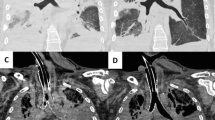

Two cases (cases 1 and 4) had ET tubes in situ, which had been placed during resuscitation prior to demise. In both of these cases, there was a leak around the tip of the airway and air was seen to distend the stomach following ventilation, and thus, they were replaced by LMAs. LMAs were successfully introduced in all patients and used for all subsequent vPMCT attempts. An LMA airway, compared to an ET tube, produced an adequate seal around the epiglottis and airway which prevented air from entering the stomach and bowel (Fig. 1). Using the LMA, no patient needed a nasogastric tube passing to reduce gastric or bowel distension. However, there were two cases of pneumothorax after PEEP vPMCT (Table 1; Fig. 2).

Example of two-stage vPMCT in a 28-day-old infant (case 6). Axial (a–c) and coronal (d–f) PMCT are shown: before ventilation (a, d), after a bag/mask ventilation (b, e) and after PEEP ventilation (c, f). The ET tube tip was in the right main bronchus prior to ventilation (black arrow) and therefore removed. A nasogastric tube is also demonstrated (white arrow)